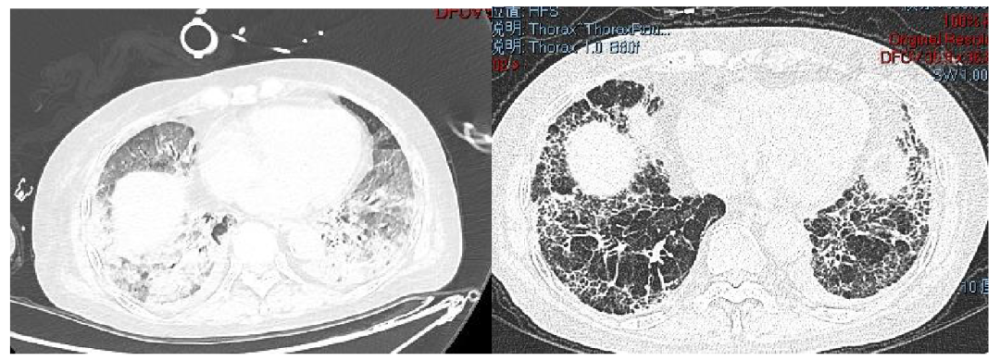

肺纖維化高發(fā)

《Nature Medicine》2021年發(fā)表了“Post-acute COVID-19 syndrome”,研究指出呼吸困難在60-100天的隨訪期內(nèi)的發(fā)生率為42%-66%,有6.6%的患者因持續(xù)低氧血癥需要補充氧氣。患者出院后3個月評估發(fā)現(xiàn)約25%的輕度至中度病例存在纖維化,在重癥病例居多的隊列中,約65%的康復(fù)者存在肺纖維化。